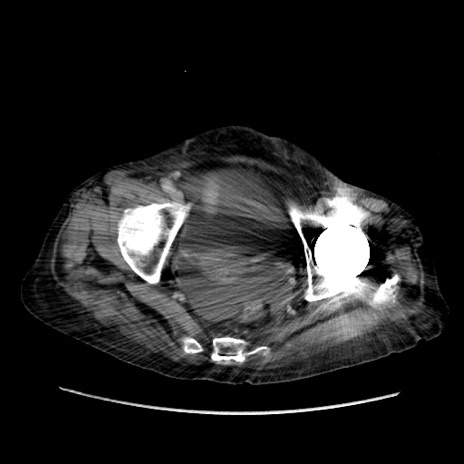

症例31(横断像)

【症例】80歳代 女性

【主訴】腹部膨満感

【現病歴】他院にて肝硬変にてフォロー中。1週間前から便秘、腹部膨満感、臍部腫瘤あり受診となる。

【既往歴】肝硬変

【身体所見】腹部膨隆あり、皮膚変化なし、疼痛なし。

【データ】WBC 4600、CRP 0.25